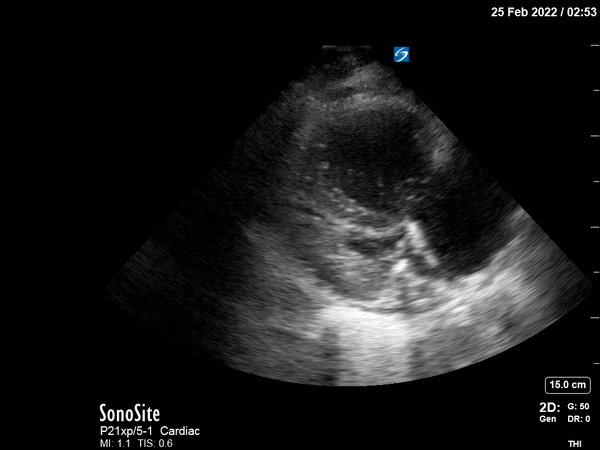

POCUS shows multiple findings consistent with acute right ventricular

(RV) systolic failure in the setting of increased RV afterload.

Parasternal long and short axis views show severe RV dilation,

flattening of the interventricular septum during systole and diastole,

and compromised LV filling. The parasternal long axis also demonstrates

dynamic obstruction of the LV outflow tract caused by systolic anterior

motion of the mitral valve (SAM), inadequate LV preload, displacement of

the interventricular septum, and tachycardia. The apical four-chamber

view shows a dilated RV with a McConnell sign (paradoxical RV apical

“hyperkinesis” in the setting of RV global hypokinesis).2